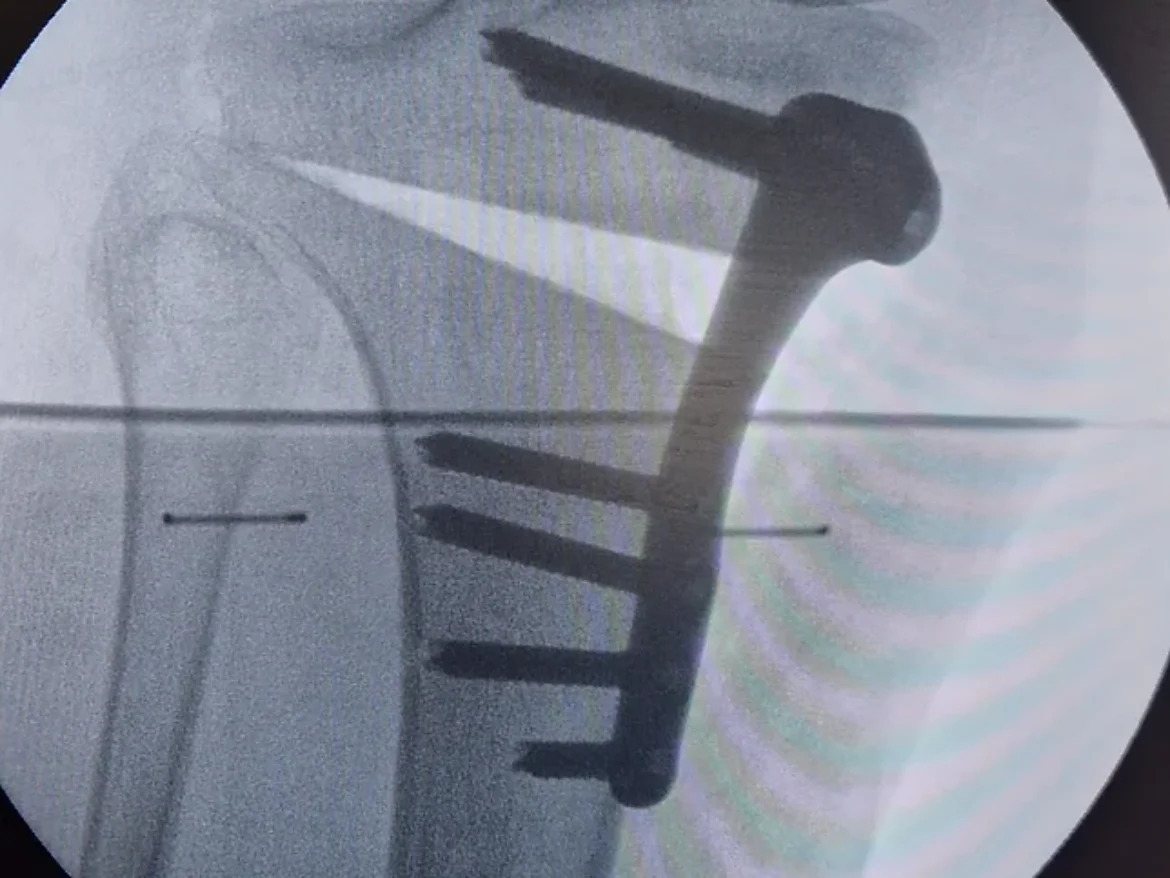

Quelques interventions :

Voici les interventions les plus fréquemment réalisées par notre équipe sur cette articulation: